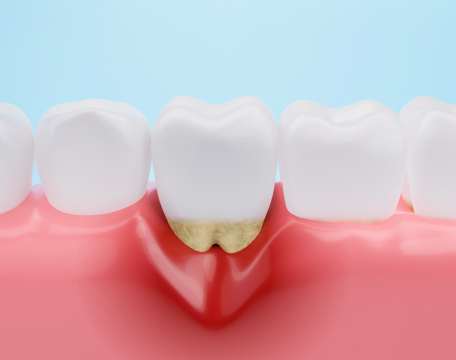

このバランスが崩れると、顎の痛み(顎関節症)や歯ぎしりだけでなく、肩こり、頭痛、姿勢の歪みなど、全身に様々な不調が現れることがあります。

当院では虫歯や歯周病の治療はもちろん、顎関節症や咬合治療、矯正、義歯、インプラントなど多岐にわたる治療を行っております。

骨格分析を基盤に、一人ひとりに合った咬合を構築することで、長期的にしっかり噛める歯並びへ。

同時に自然な見た目を追求し、日常生活の質を高めます。